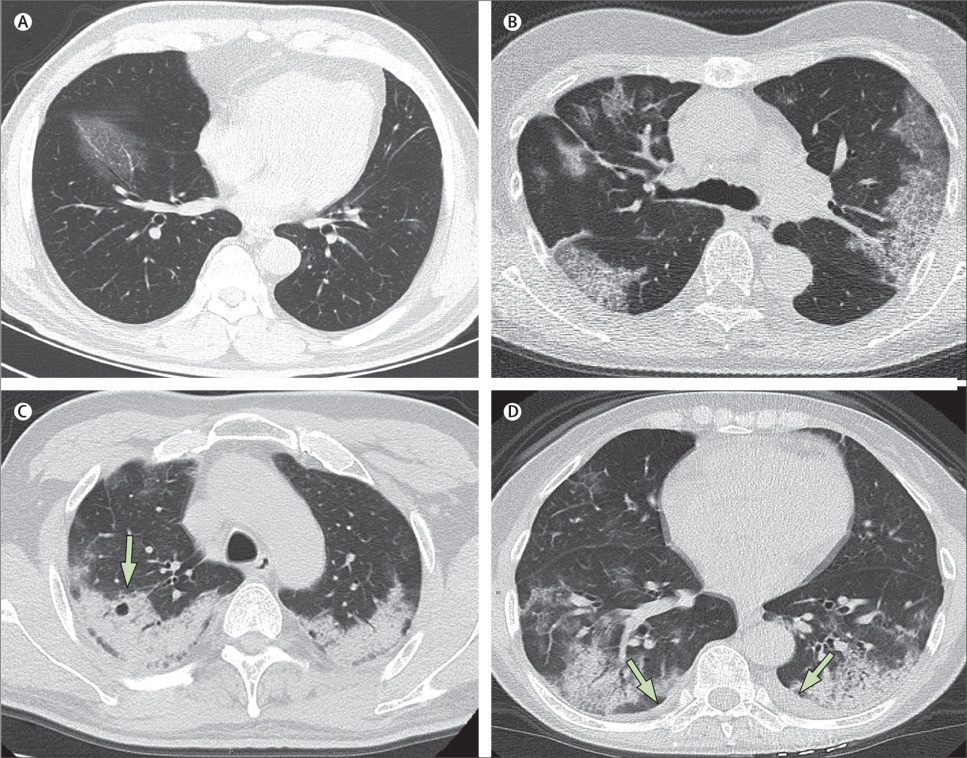

virus corona lan rong anh 2

Hình ảnh CT phổi này là của một bệnh nhân 50 tuổi qua đời ngày 27/1 sau 2 tuần điều trị tại Trung Quốc. Tim bệnh nhân ngừng đập sau khi bị tổn thương phế nang. Trước đó, các bác sĩ tại Trung Quốc cho bệnh nhân điều trị bằng thuốc gồm điều trị chống nhiễm trùng interferon alfa-2b, thuốc AIDS lopinavir - ritonavir và kháng sinh moxifloxacin để ngừa nhiễm trùng thứ cấp. Ngoài ra, bác sĩ cũng chỉ định steroid methylprednisolone để điều trị tình trạng viêm phổi, khó thở và thiếu oxy trong máu. Ảnh: The Lancet.

virus corona lan rong anh 4

Hình CT chụp phổi của các bệnh nhân Covid-19 tại Trung Quốc.Hình A: Bệnh nhân nam 56 tuổi, ngày thứ 3 sau khi khởi phát triệu chứng, phổi xuất hiện các đốm trắng từ vách liên sườn đến nội nhãn ở thùy dưới bên phải. Hình B: Bệnh nhân nữ 74 tuổi, ngày thứ 10 sau khi khởi phát triệu chứng: hai bên phổi dày đặc những đốm trắng chứng tỏ sự xâm chiếm và phá hủy nặng của virus corona tới các phế nang. Hình C: Nữ bệnh nhân 61 tuổi, ngày 20 sau khi khởi phát triệu chứng: phổi bị bao phủ bởi lớp trắng mờ đục dày, các phế nang bên trong đã bắt đầu biến đổi. Hình D: Nữ bệnh nhân 63 tuổi, ngày 17 sau khi khởi phát triệu chứng: hai bên phổi xuất hiện lớp đốm trắng dày trong phế quản ở cả thùy dưới lẫn thùy trên, đã có hiện tượng tràn dịch màng phổi. Ảnh: The Lancet.